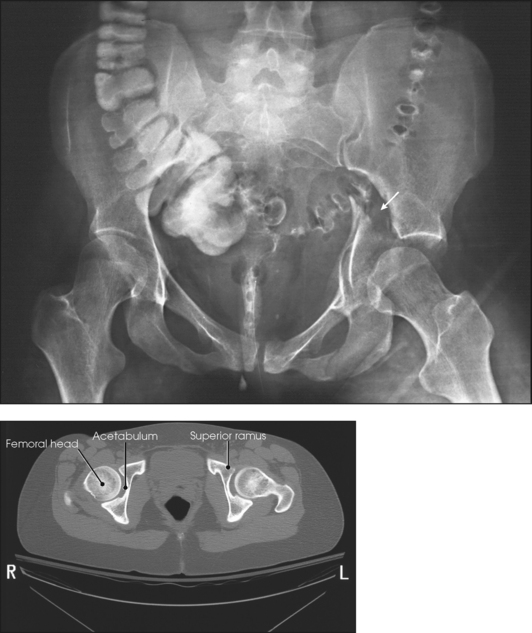

The hip bone consists of the ilium, pubis, and ischium (Figs. 7-1 and 7-2). These three bones join together to form the acetabulum, the cup-shaped socket that receives the head of the femur. The ilium, pubis, and ischium are separated by cartilage in children but become fused into one bone in adults.

Fig. 7-3 Axial CT image of inferior ramus and ischial tuberosity. (Modified from Kelley L, Petersen CM: Sectional anatomy for imaging professionals, ed 2, St Louis, 2007, Mosby.)

The ischium consists of a body and the ischial ramus. The body of the ischium forms approximately two fifths of the acetabulum posteriorly (see Figs. 7-2 and 7-3). It projects posteriorly and inferiorly from the acetabulum to form an expanded portion called the ischial tuberosity. When the body is in a seated-upright position, its weight rests on the two ischial tuberosities. The ischial ramus projects anteriorly and medially from the tuberosity to its junction with the inferior ramus of the pubis. By this posterior union the rami of the pubis and ischium enclose the obturator foramen. At the superoposterior border of the body is a prominent projection called the ischial spine. An indentation, the lesser sciatic notch, is just below the ischial spine.